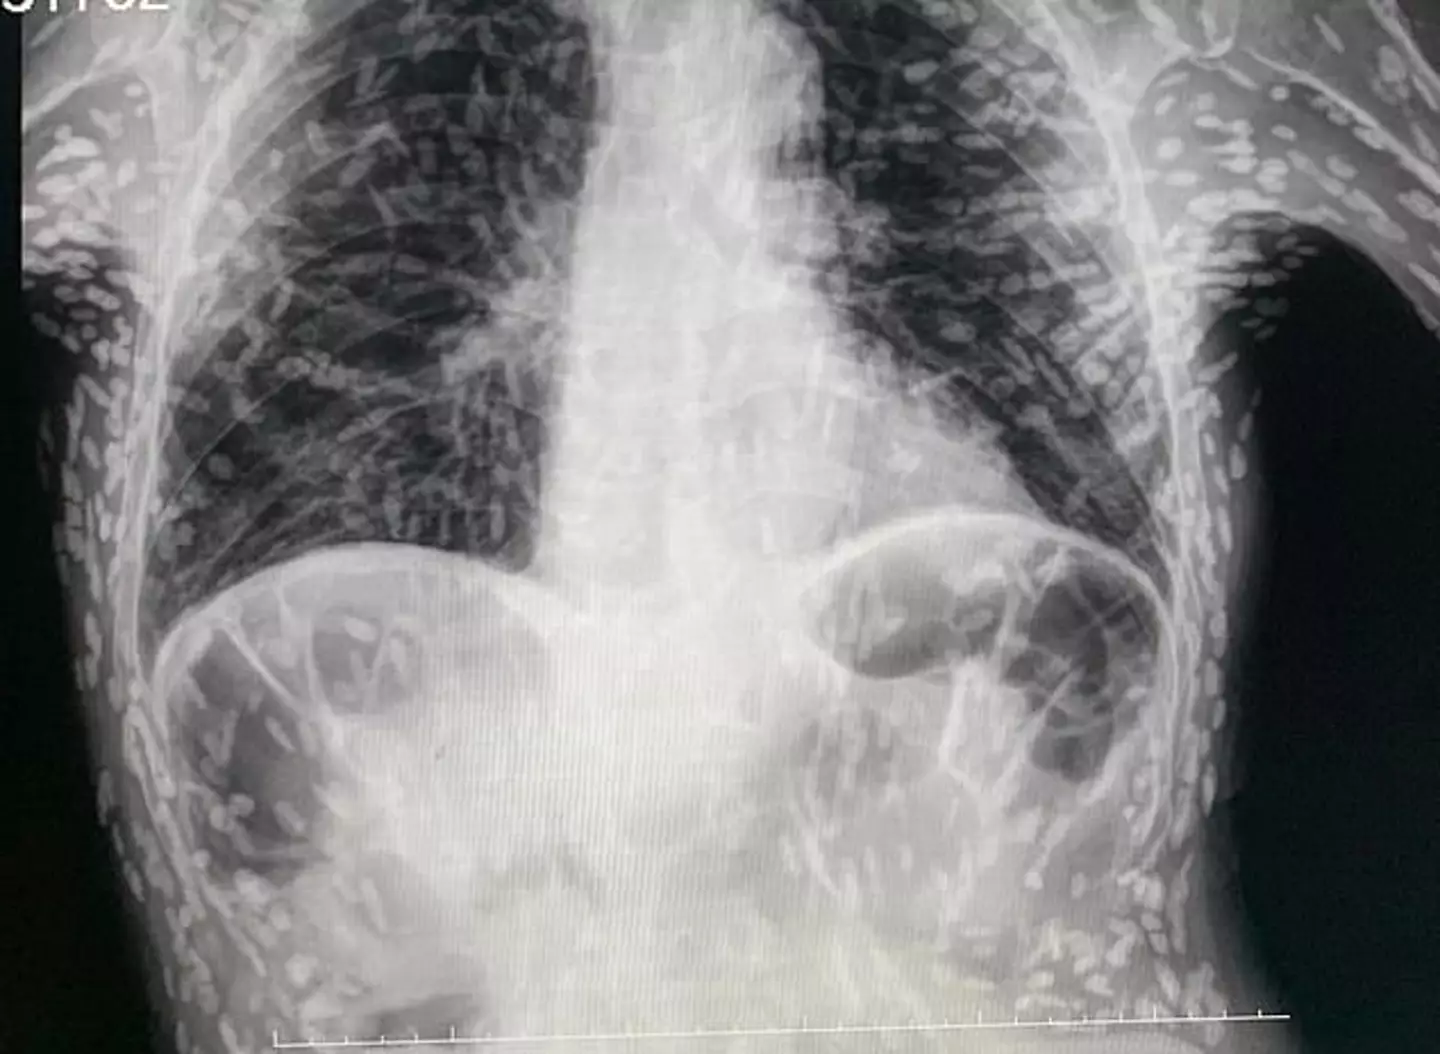

A horrifying x-ray of the discovery was shared on Twitter by Dr Vitor Borin P. de Souza, a practitioner at the Hospital das Clínicas Botucatu in São Paulo, Brazil.

Each of the white dots on the horrifying x-ray image represents a cyst and the calcified remains of a parasite.

Cysts can take months or even years to develop after the ingestion of the tapeworm eggs eggs but can be removed easily through surgery or medication.